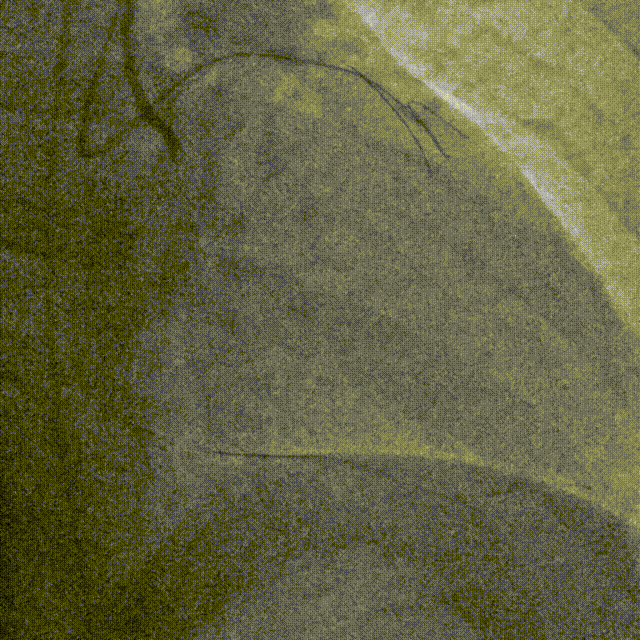

复查造影并行ivus检查 支架贴壁良好 无累及夹层。

RCA中段扩张后出现夹层,植入DES。